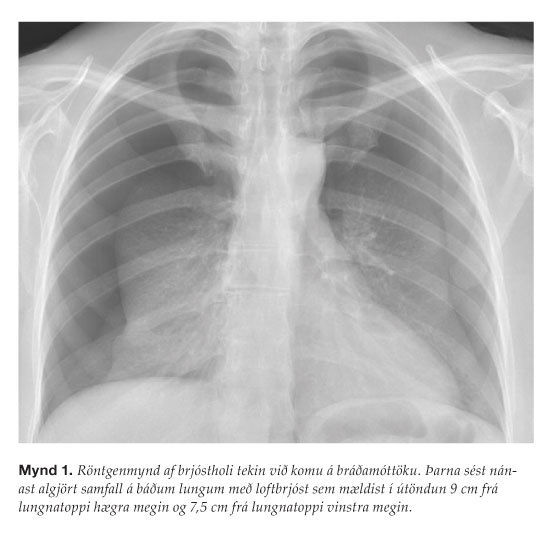

Kona á fertugsaldri sem hafði gengið með í tæpar 15 vikur leitaði á bráðamóttöku Landspítala vegna skyndilegrar mæði og takverks. Hún hafði glímt við ógleði og uppköst á meðgöngunni og því var reynd nálastungumeðferð sem framkvæmd var utan spítala. Að sögn sjúklingsins var fíngerðum nálum stungið neðan við herðablöð beggja vegna, aftan við axlir, en einnig í framanverðan brjóstkassa og neðri útlimi. Strax eftir stungurnar fann hún fyrir mæði og takverk sem ágerðust á næstu klukkustundum. Einkennin héldu áfram að versna og því leitaði hún á bráðamóttöku um 7 klukkustundum eftir nálastungumeðferðina. Við lungnahlustun heyrðust minnkuð öndunarhljóð yfir lungnatoppum beggja vegna. Öndunartíðni var 26/mín í hvíld (viðmið 12-20/mín), súrefnismettun 100% án súrefnis, púls mældist 99/mín og blóðþrýstingur 112/73 mmHg. Á röntgenmynd af lungum sást nánast algjört samfall á báðum lungum með ívið stærra loftbrjósti hægra megin ( mynd 1 ). Blóðrannsóknir voru eðlilegar nema hvít blóðkorn sem voru hækkuð (15,9 x109/L) og kalíum sem var lækkað (3,0 mmól/L). Skömmu eftir komu var brjóstholskerum komið fyrir í bæði fleiðruhol sem tengdir voru við sog og þöndust bæði lungu út við það ( mynd 2 ).